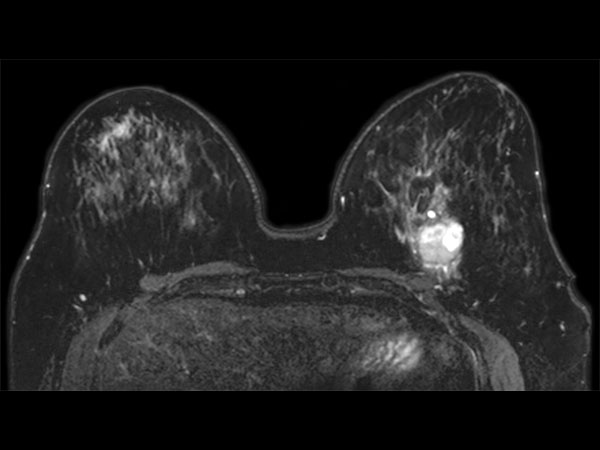

57 year old female with a new diagnosis of Ca. Sample obtained by US biopsy: Invasive Ductal Ca, grade 3. MR requested to aid in determining treatment.

Dynamic axial eTHRIVE